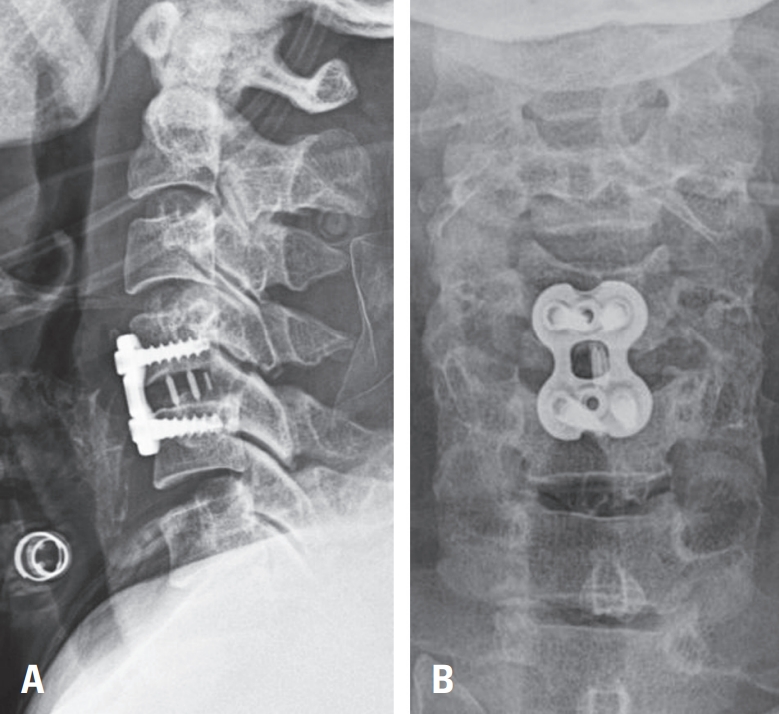

Fig. 1D). As there were no acute posterior circulation symptoms, the patient underwent urgent anterior cervical discectomy and fusion (ACDF) at C4–C5 to relieve cord compression (

Fig. 2A,

B).

Fig. 2.

(A, B) Postoperative cervical spine radiographs (anteroposterior and lateral views) demonstrating anterior cervical discectomy and fusion (ACDF) at C4–C5.